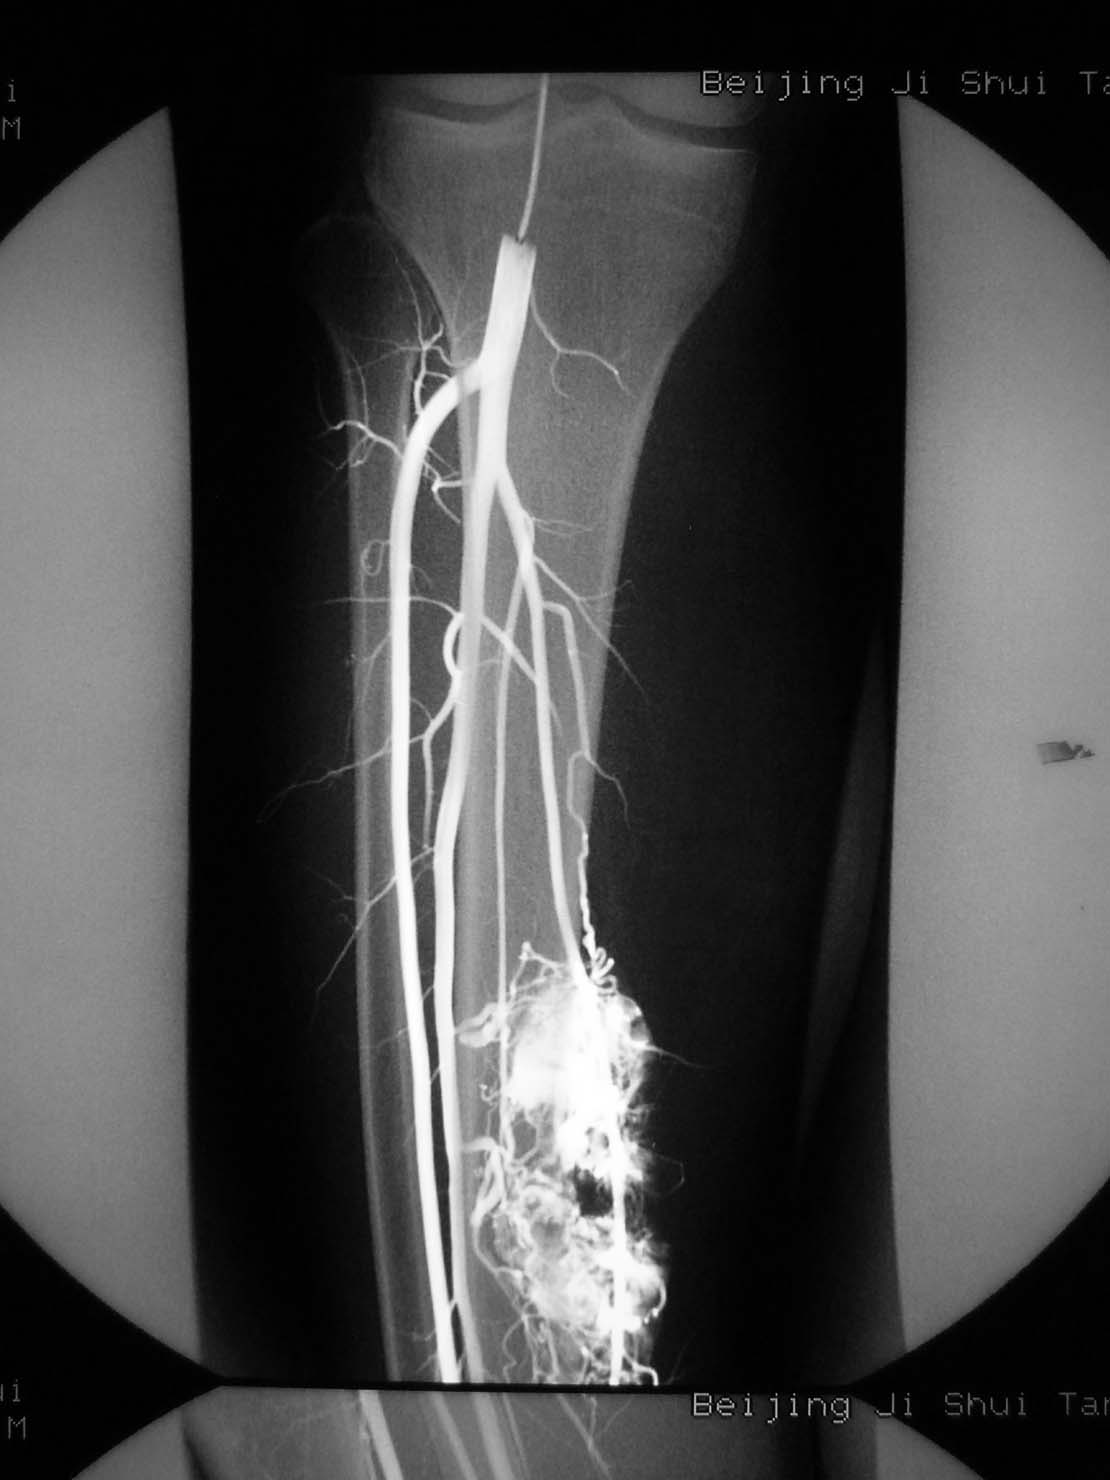

病理结果,腺泡样软组织肉瘤!

腺泡样软组织肉瘤

极为罕见,其组织来源不明。

起源于肢体软组织者称腺泡状软组织肉瘤,原发于骨内者,称骨腺泡状肉瘤。

本病大多发生于股部、臀部及小腿深侧肌群,上肢和其他部位少见。

x线平片:圆形或卵圆形软组织肿块影,基底部与病骨相连。

肿瘤内可见斑点状或细小结节状钙化。

骨质破坏大多表现为溶骨性地图状或虫噬性破坏,并常伴有层状骨膜反应。

mr检查:t1和t2加权像均显示肿瘤组织呈分叶状高信号强度,并见肿瘤内有低信号间隔。